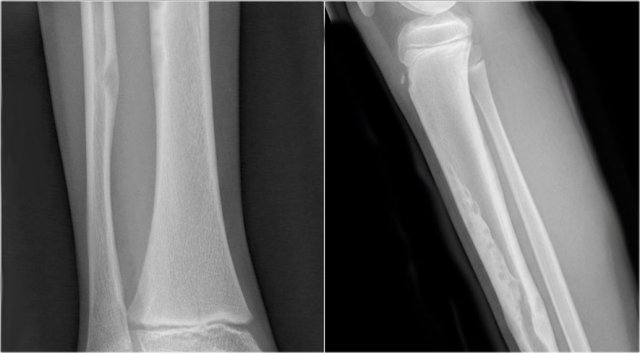

ABC (6) - atypical case

On the left two different patients with an intracortical or subperosteal osteolytic well-defined lesion in the tibia.

The lesion on the far left was thought to be an adamantinoma because of the localisation in the anterior tibial cortex.

At biopsy it proved to be an ABC.

The image on the right is an adamantinoma.